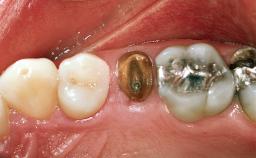

Replacement of a Maxillary Right Central Incisor Using an Early Loading Protocol

A healthy 26-year-old woman was referred for evaluation and treatment of her failing maxillary right central incisor (tooth 11). She reportedly traumatized the tooth at about age 9 and subsequently had repeated conventional and surgical endodontic procedures and fixed restorations. Despite these procedures, she had recurrent fistulas in the apical mucosa and a mid-facial pocket of 7 mm with suppuration. All other sites on the tooth probed 3 mm without inflammation. She presented with a medium biotype with triangularlyshaped teeth and a moderately high smile line, showing all of her papillas and a few millimeters of marginal gingiva in a full smile.Ceramic veneers were present on teeth 12, 21, and 22, and they were known to be somewhat bulky, eventually requiring replacement. She had a strong desire to avoid additional tooth preparation and would not consider a fixed dental prosthesis to replace tooth 11.

Prosthodontic Status of Neighboring Teeth Virgin Restored

Width of Edentulous Span 1 tooth (>= 7 mm) 1 tooth (< 7 mm) 2 teeth or more